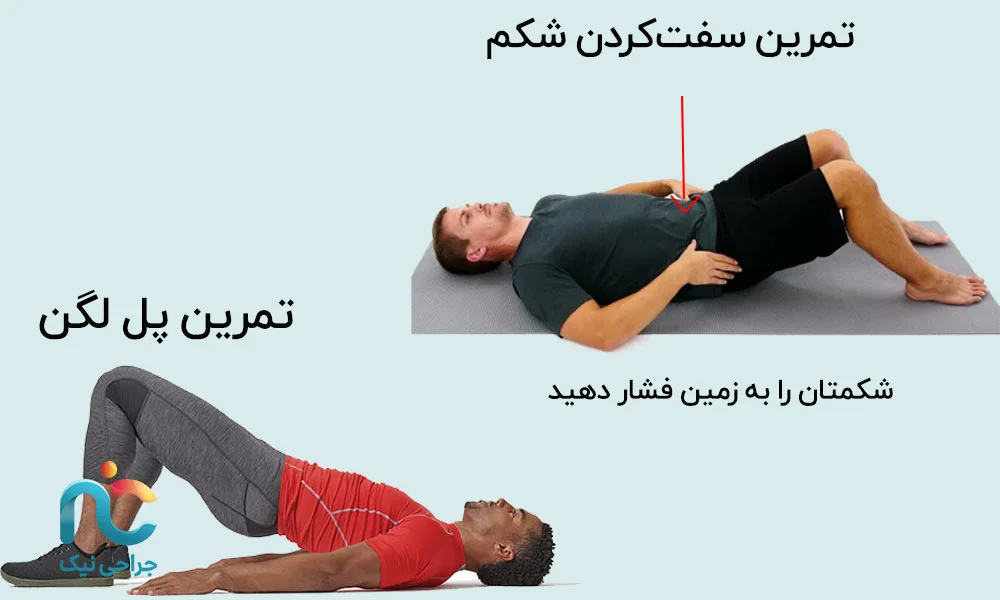

در هفته دوم، بدن شما معمولاً به تزریق عادت کرده است و درد تا حدی قابلتحملتر شده است. این همان زمانی است که باید از آن برای بیدار کردن و تقویت ملایم عضلات مرکزی بدن استفاده کنید؛ منظور از عضلات مرکزی، عضلات شکم، کمر و اطراف لگن است که مثل یک کمربند طبیعی از ستون فقرات شما محافظت میکنند.

در این هفته، روزانه حدود ده تا پانزده دقیقه را به تمرینهای ساده اختصاص میدهید؛ تمرینهایی که فشار ناگهانی به کمر نمیآورند. مثلا میتوانید در حالت خوابیده به پشت، زانوها را خم کنید، کف پاها را روی تشک قرار دهید و فقط شکم را به آرامی سفت کنید، بهطوری که کمرتان را به تشک نزدیکتر حس کنید، و این وضعیت را پنج تا ده ثانیه نگه دارید و چند بار تکرار کنید. در یک تمرین دیگر، در همین حالت، میتوانید لگن را کمی بالا بیاورید و مانند یک پل کوچک، تنه و لگن را برای چند ثانیه نگه دارید و دوباره روی تشک برگردانید. این حرکات نباید درد تیرکشندهی پا را تشدید کنند؛ اگر درد تیز شد، همانجا متوقف میشوید و در جلسهی بعدی با پزشک یا فیزیوتراپیست مطرح میکنید.

در این هفته، تمرینهای تقویت عضلات عمقی کمر و شکم را دو بار در روز انجام میدهید؛ هر بار حدود ده تا پانزده دقیقه. لازم نیست شدت تمرین زیاد باشد—مهم «کنترل، نظم و دقت» است.

یکی از تمرین های مناسب حرکت مرغ-سگ است. برای انجام، روی دستها و زانو قرار بگیرید و ستون فقرات را در وضعیت طبیعی نگه دارید. دست راست را به جلو و پای چپ را همزمان به عقب بکشید. بدن باید ثابت بماند؛ نگذارید کمر بچرخد یا لگن به یک طرف بیفتد. چند ثانیه مکث کنید و آرام به حالت اول برگردید، سپس با سمت دیگر تکرار کنید. این تمرین عضلات عمقی ستون فقرات و لگن را فعال میکند و یکی از بنیادیترین حرکات برای پیشگیری از بازگشت درد است. روزی یک تا دو بار، هر طرف پنج تا هشت بار کافی است.

حرکت کشش پشت ران هم حرکت مناسب دیگری ست که می توانید در این دوره انجام دهید. روی زمین بخوابید، یک پا را دراز کنید و پای دیگر را با دو دست آرام به سمت سینه بکشید. باید در پشت ران احساس کشش ملایمی داشته باشید، نه درد شدید یا تیرکشنده. کمر روی زمین بماند و حرکت کاملاً نرم باشد. این کشش کمک میکند عضلات پشت ران که معمولاً در افراد کمردردی کوتاه و سفت هستند، آزاد شوند و فشار از روی کمر برداشته شود. هر پا را روزی دو تا سه بار، ۱۵ تا ۲۰ ثانیه نگه دارید.

حرکت گربه–گاو مهرهها را نرم میکند و تنش عضلات را کم میکند. برای انجام این حرکت، روی دستها و زانو قرار بگیرید. در حرکت «گاو»، شکم را پایین ببرید، کمر را بهآرامی گود کنید و نگاه را کمی بالا بگیرید.

در حرکت «گربه»، کمر را به سمت بالا قوس دهید، شکم را جمع کنید و سر را پایین بیاورید. حرکت باید کاملاً آرام، پیوسته و بدون فشار انجام شود. روزی ۱۰ تا ۱۵ بار کافی است.

تمرین تعادل تکپا عضلات کوچک تثبیتکننده لگن و کمر را فعال میکند و به بهبود تعادل و کنترل بدن کمک زیادی میکند. برای انجام این حرکت، صاف بایستید و یکی از پاها را آرام از زمین بلند کنید. بدن را ثابت نگه دارید و اجازه ندهید لگن کج شود. نگاهتان به یک نقطه ثابت مقابل باشد. در هفته سوم هر پا را روزی دو تا سه بار، ۱۰ تا ۲۰ ثانیه نگه دارید.

این هفته بهترین زمان برای تبدیل کردن «حرکات درست» به «عادت دائمی» است. نحوه بلند کردن صحیح اجسام باید در این هفته باید برایتان عادت شود. چه یک کیف سبک باشد، چه یک جسم سنگینتر، همیشه اول زانوها را خم کنید، کمر را صاف نگه دارید و جسم را نزدیک بدن نگهدارید. این روش ساده یکی از قویترین راههای جلوگیری از آسیب دوباره است.